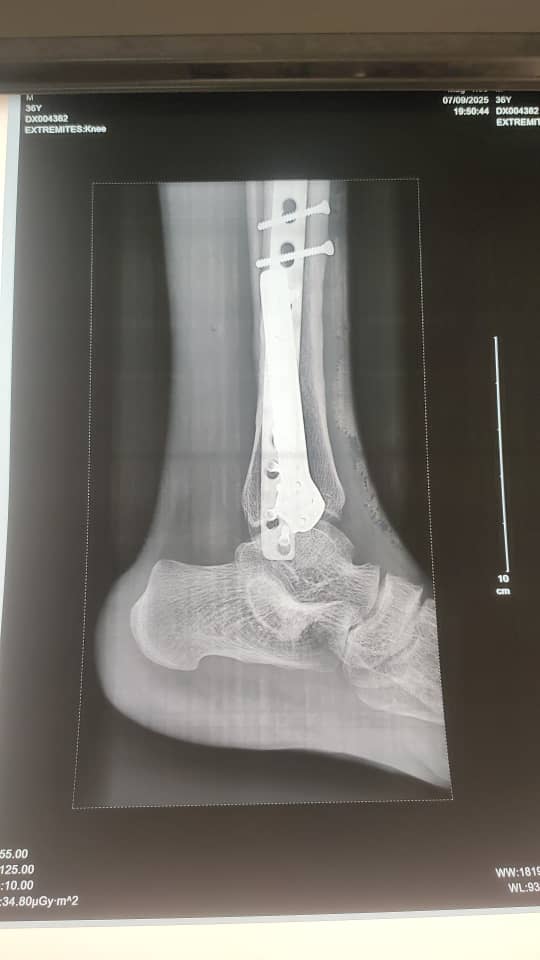

Galerie d’implants & imagerie

Exemples pédagogiques de prothèses et d’ostéosynthèses pratiquées à la CCL.

Cheville — plaque latérale

Cheville — post-op